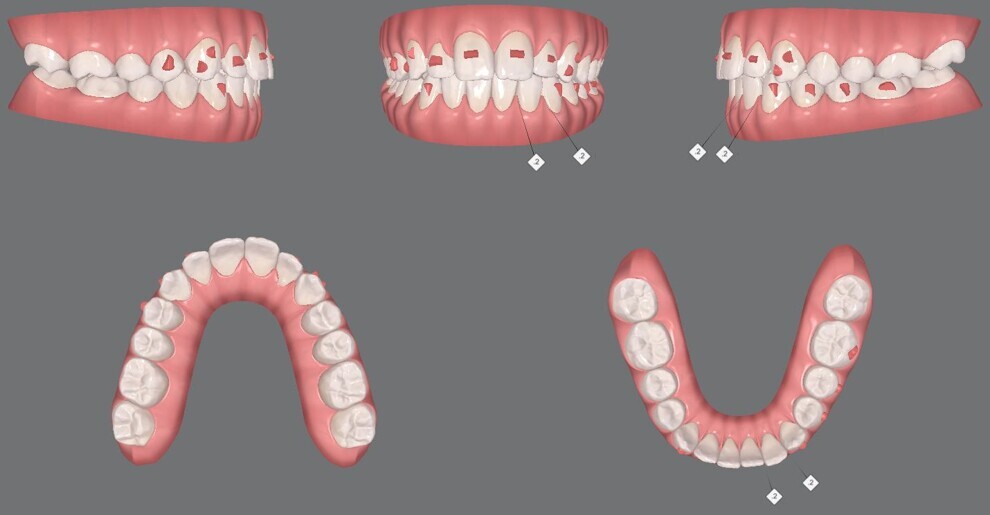

Figs. 12a–e: Pre-aligner treatment digital models

Figs. 14a–e: Mid-treatment digital models.

Figs. 24a–e: Final digital models.